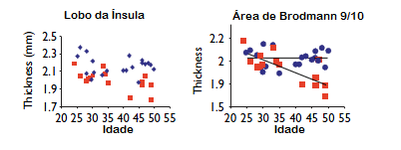

Adicionalmente, a meditação pode retardar a diminuição do córtex frontal causada pelo envelhecimento do indivíduo.  Os gráficos ao lado mostram a média da espessura cortical de cada participante em duas regiões distintas do cérebro em relação às suas idades. Os participantes que meditavam estão representados pelos pontos azuis enquanto aqueles do grupo de controle estão representados pelos pontos vermelhos. Repare que os participantes que meditavam mantêm a sua espessura cortical ao longo da vida, enquanto aqueles que não meditam sofrem um decréscimo nestas regiões.

Os gráficos ao lado mostram a média da espessura cortical de cada participante em duas regiões distintas do cérebro em relação às suas idades. Os participantes que meditavam estão representados pelos pontos azuis enquanto aqueles do grupo de controle estão representados pelos pontos vermelhos. Repare que os participantes que meditavam mantêm a sua espessura cortical ao longo da vida, enquanto aqueles que não meditam sofrem um decréscimo nestas regiões.